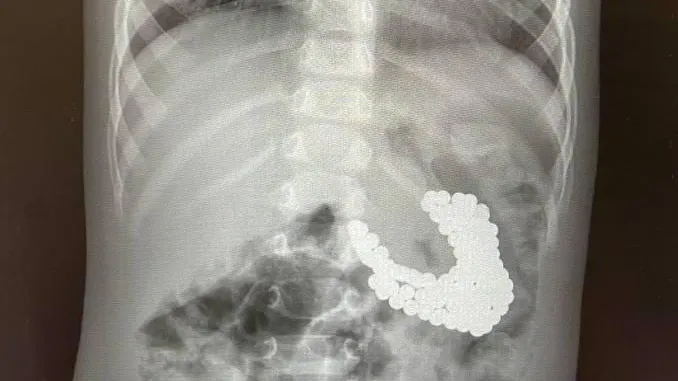

Полуторагодовалый мальчик поступил в детский медцентр имени Рошаля в Красногорске с подозрением на проглатывание инородных тел. Врачи обнаружили у него в желудке скопление большого количества магнитов и батарейку. Это могло привести к ожогам, некрозу тканей и кровотечению.

По словам заведующего эндоскопическим отделением центра Александра Иноземцева, из желудка мальчика извлекли 130 магнитов. Они сцепились друг с другом, из-за чего слизистая оболочка повредилась и образовалась язва.

При помощи специальных инструментов маленькому пациенту провели гастроскопию, в ходе которой инородные тела последовательно извлекли из желудка. После операции рентген выявил еще три магнита, которые удалось извлечь лишь хирургическим путем.

«Ребенок глотал магниты в разное время, поэтому некоторые из них уже переместились в кишечник. Находясь там, они сцепились и притянули друг к другу желудок и кишечник. Извлечь оставшуюся часть можно было только хирургическим путем», — объяснил врач.